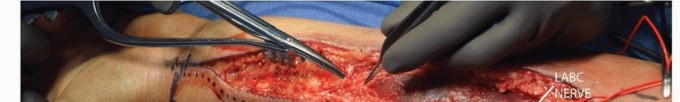

Anterior (Volar) Approach to the Radius Light exsanguination is performed by elevation or loose wrapping with a sterile Ace wrap and the tourniquet is inflated. The incision is drawn centered on the fracture from the lateral edge of the biceps tendon to the radial styloid. Length depends on the degree of comminution but in general will comprise approximately one-third of the forearm length (TECH FIG 1A). An incision is made through the skin only, followed by blunt dissection down to the fascia. Attention is paid to visualization of the lateral antebrachial cutaneous nerve (TECH FIG 1B). (We generally score the skin with our knife blade then deepen the incision with a needle tip cautery through the dermis to aid in hemostasis at the skin level.) Small branches of the lateral antebrachial cutaneous nerve if encountered are sacrificed to mobilize the main nerve out of the field of dissection. A sponge can be used to sweep away the deep fat off the fascia if needed. The fascia is incised and released with scissors. The radial artery and venae comitantes must be identified and mobilized. In the proximal third of the forearm, the radial artery lies deep to the brachioradialis muscle belly, which at this level nears the midline of the anterior forearm. Bipolar cauterization of perforators to the brachioradialis muscle allows mobilization of the radial artery medially. In the middle third of the forearm, the radial artery is more superficial—often in a layer of fat just beneath the fascia—as it exits the interval between brachioradialis muscle belly and flexor carpi radialis muscle belly (TECH FIG 1C). Again, the artery is mobilized medially.

TECH FIG 1 • Anterior approach to the radius. A. The forearm is mentally divided in thirds. Each third has unique anatomic structures that must be recognized during the approach. Extensile exposure extends from the biceps tendon to the radial styloid. Distal-third fractures can alternatively be approached through the floor of the flexor carpi radialis (FCR) tendon. B. Blunt dissection is performed superficially, and the main trunk of the lateral antebrachial cutaneous nerve (LABC) is identified and protected. (continued) In the distal third of the forearm, it is sometimes safer to mobilize the radial artery laterally, and in the very distal forearm, the approach can be made through the floor of the flexor carpi radialis, thereby avoiding the radial artery completely. In the proximal forearm, the muscular envelope is deep, and dissection proceeds along the medial edge of brachioradialis. The superficial radial nerve is identified, and care is taken not to place retractors directly on the nerve. The supinator will be identified by the oblique muscle fiber orientation, and the surgeon must be mindful that the PIN runs proximal-medial to distal-lateral, entering 90 degrees to the orientation of the muscle fibers and fascia. With the radius broken, it is difficult to effectively supinate the proximal forearm in order to protect the PIN. If the bone is exposed distal to the supinator, a reduction forceps can be placed on the bone and the assistant can supinate the proximal radius. This allows the muscle to be peeled with a freer elevator or knife in a medial to lateral direction, safely keeping the PIN laterally. Alternatively, the PIN can be identified, although this is usually not necessary. When dissecting near the biceps tuberosity, usually, a small amount of clear, thick fluid from the biceps bursae will be released as dissection nears the biceps insertion. This burst of fluid is helpful in orienting the surgeon to their location. Just proximal to this, there are typically multiple crossing vessels that need not be disturbed. They can be retracted en masse with a blunt retractor if necessary. The most efficient dissection to the middle and distal thirds of the radius proceeds down to its lateral border. Proximally, where the supinator lies the dissection on the medial radius avoids the PIN. In the middle third of the radius, the flexor digitorum profundus and pronator teres can be sharply released from lateral to medial. The pronator teres can be Z-lengthened or taken off the bone in a subperiosteal fashion. Alternatively, if only a limited amount of exposure is needed, its muscle fibers can be dissected off the tendinous portion for a short distance, leaving the tendon intact. If taken off the radius, it can be sutured back down to the plate (TECH FIG 1D). Our preference is the latter during extensile exposures. Distally, the flexor pollicis longus and pronator quadratus are taken off the radius laterally to medially with a knife. Bone fixation techniques are then performed as described in the following text (TECH FIG 1G). The tourniquet is always taken down. If a meticulous dissection has been performed with liberal use of bipolar cautery, little bleeding is encountered. Fascia is not closed, but inverted interrupted absorbable monofilament suture is used as needed to reapproximate the subcutaneous tissues followed by 3-0 nylon suture for the skin.